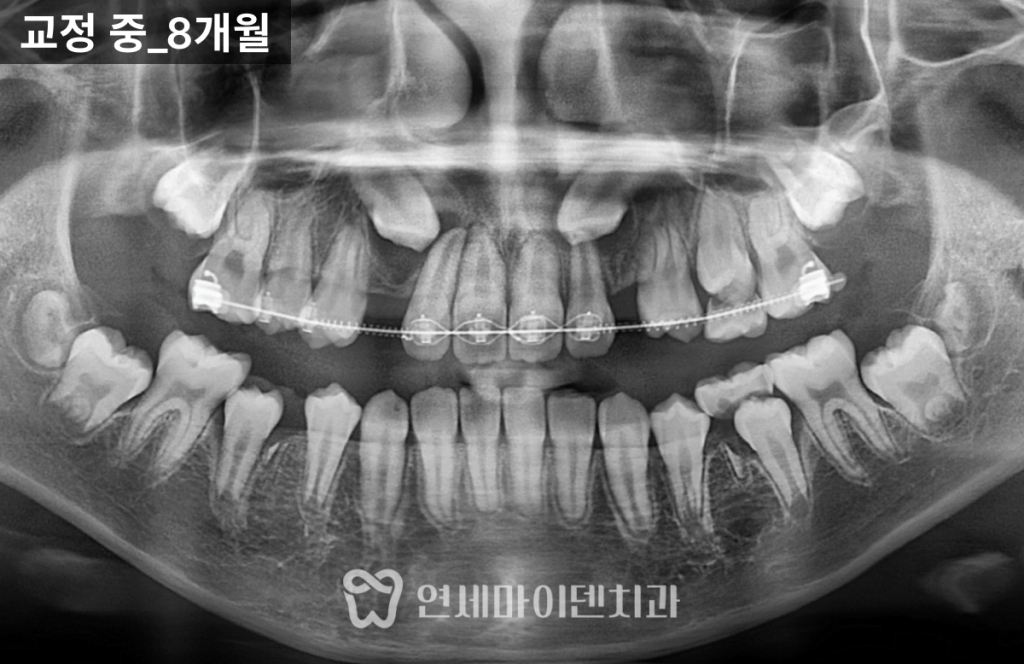

치료과정

1️⃣초기엔 앞니와 어금니에 부분 장치를 부착해

송곳니가 내려올 공간을 확보했습니다.

2️⃣오른쪽 송곳니는 공간을 확보해

자발적으로 위치를 찾아 내려오기 시작했습니다.